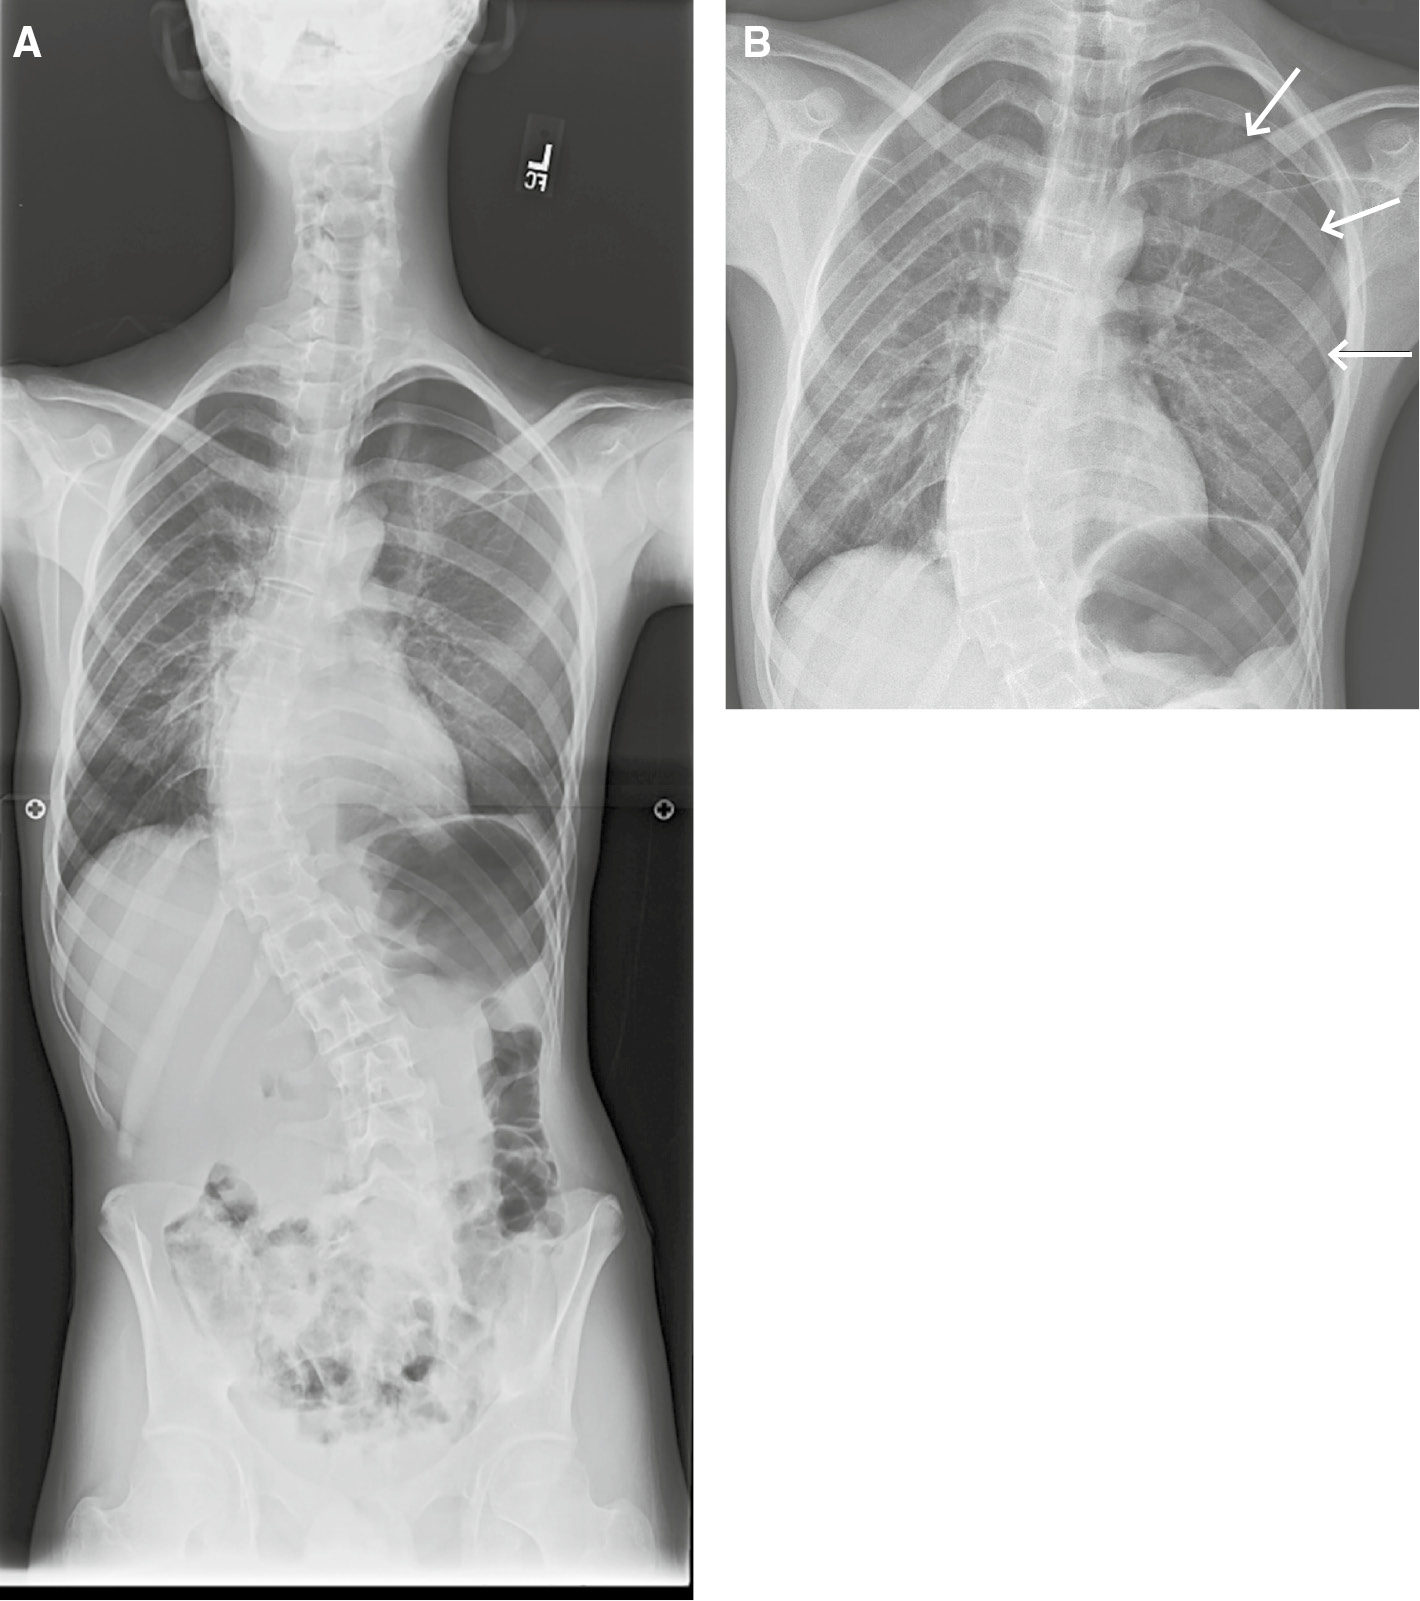

Figure 4: Inattentional blindness error.Frontal radiograph of the entire spine (A) obtained for monitoring of scoliosis in a 15-year-old male with upper back pain. An unexpected, large left pneumothorax (B, arrows) was missed.

Figure 4:

Inattentional blindness error.

Frontal radiograph of the entire spine (A) obtained for monitoring of scoliosis in a 15-year-old male with upper back pain. An unexpected, large left pneumothorax (B, arrows) was missed.

Failure to identify the absence of an expected image feature is another manifestation of inattentional blindness. In one study, radiologists were shown chest X-rays with a clavicle removed. When no cues were given, approximately 60% of radiologists failed to identify the abnormality. When historical cues were added (e.g. chest X-ray for metastatic survey) the detection rate increased to 83% [22] (Figure 4).